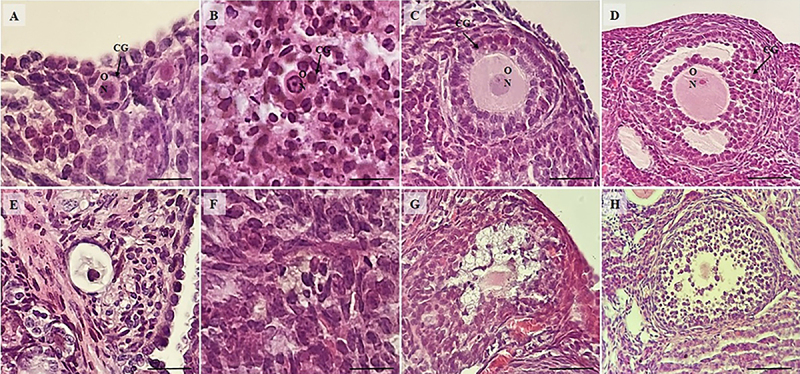

本研究旨在评价芦荟对阿霉素(DOX)诱导的小鼠卵巢卵泡和基质细胞变性的保护作用。48只小鼠随机分为6组。阳性对照组小鼠口服n -乙酰半胱氨酸(po)预处理,1h后单次腹腔注射DOX (NAC+DOX)。阴性对照组小鼠经生理盐水(po)预处理,1 h后给予单剂量DOX (SAL+DOX)。其他各组小鼠分别以不同浓度预处理(0.1、1.0、10.0 mg/kg;po),然后在1 h后接受单剂量DOX (AV0.1+DOX, AV1.0+DOX和AV10.0+DOX)。对照组给予生理盐水po、ip (SAL+SAL)。芦荟每天1次,连续3天。第4天,对卵巢进行组织学分析、免疫组化、实时荧光定量PCR (real-time PCR)检测超氧化物歧化酶(SOD)、过氧化氢酶(CAT)、核因子-红细胞2相关因子2 (NRF2)、肿瘤坏死因子-α (TNF-α) mRNA。结果表明,0.1和1.0 mg/kg芦荟对dox诱导的卵巢变性具有保护作用。此外,0.1和1.0 mg/kg芦荟可降低TNF-α蛋白表达,提高NRF2、SOD和CAT mRNA水平。综上所述,0.1和1.0 mg/kg芦荟对dox诱导的小鼠卵巢卵泡和间质细胞变性具有保护作用。

The present study aimed to evaluate the protective effects of Aloe vera on doxorubicin (DOX)-induced degeneration in ovarian follicles and stromal cells in mice. Mice (n=48) were randomly divided into six groups. The positive control group mice received pretreatment of N-acetylcysteine orally (po), followed by a single intraperitoneal (ip) dose of DOX after 1 h (NAC+DOX). The negative control group mice were pre-treated with saline (po) and administered a single DOX dose (ip) after 1 h (SAL+DOX). The other groups of mice were pre-treated with different concentrations (0.1, 1.0, or 10.0 mg/kg; po) of Aloe vera and then received a single dose of DOX (ip) after 1 h (AV0.1+DOX, AV1.0+DOX, and AV10.0+DOX). The control group received saline po and ip (SAL+SAL). Aloe vera was administered once daily for 3 consecutive days. On the fourth day, the ovaries were processed for histological analysis, immunohistochemistry, and real-time PCR (mRNA for superoxide dismutase (SOD), catalase (CAT), nuclear factor erythroid 2-related factor 2 (NRF2), and tumor necrosis factor-α (TNF-α). Results showed that 0.1 and 1.0 mg/kg Aloe vera protected ovarian follicles and stromal density against DOX-induced degeneration. Furthermore, 0.1 and 1.0 mg/kg Aloe vera reduced TNF-α protein expression and increased NRF2, SOD, and CAT mRNA levels. In conclusion, 0.1 and 1.0 mg/kg Aloe vera had protective effects against DOX-induced degeneration in ovarian follicles and stromal cells in mice.